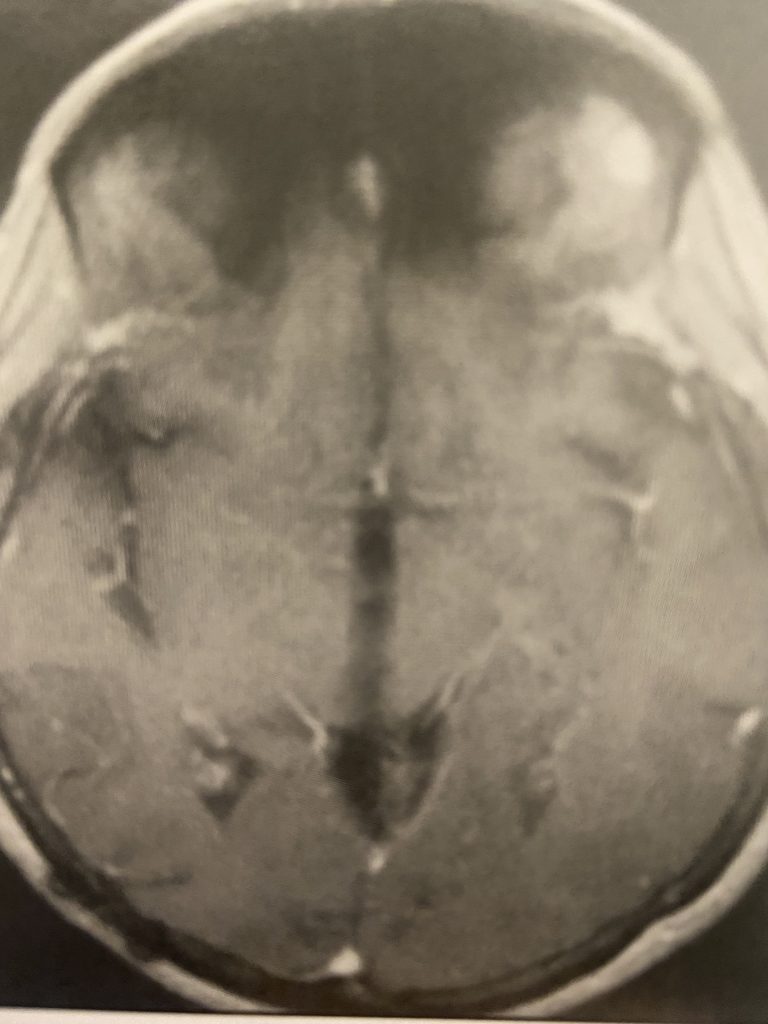

Subsequently, the hydrocephalus resolved and the patient did not require shunting. Her pre-operative symptoms all resolved. Follow up MRI demonstrated complete removal of the tumor.

Figure 3

Figure 4

Postoperative post contrast axial MRIs demonstrating complete removal of the tumor with resolution of the hydrocephalus.